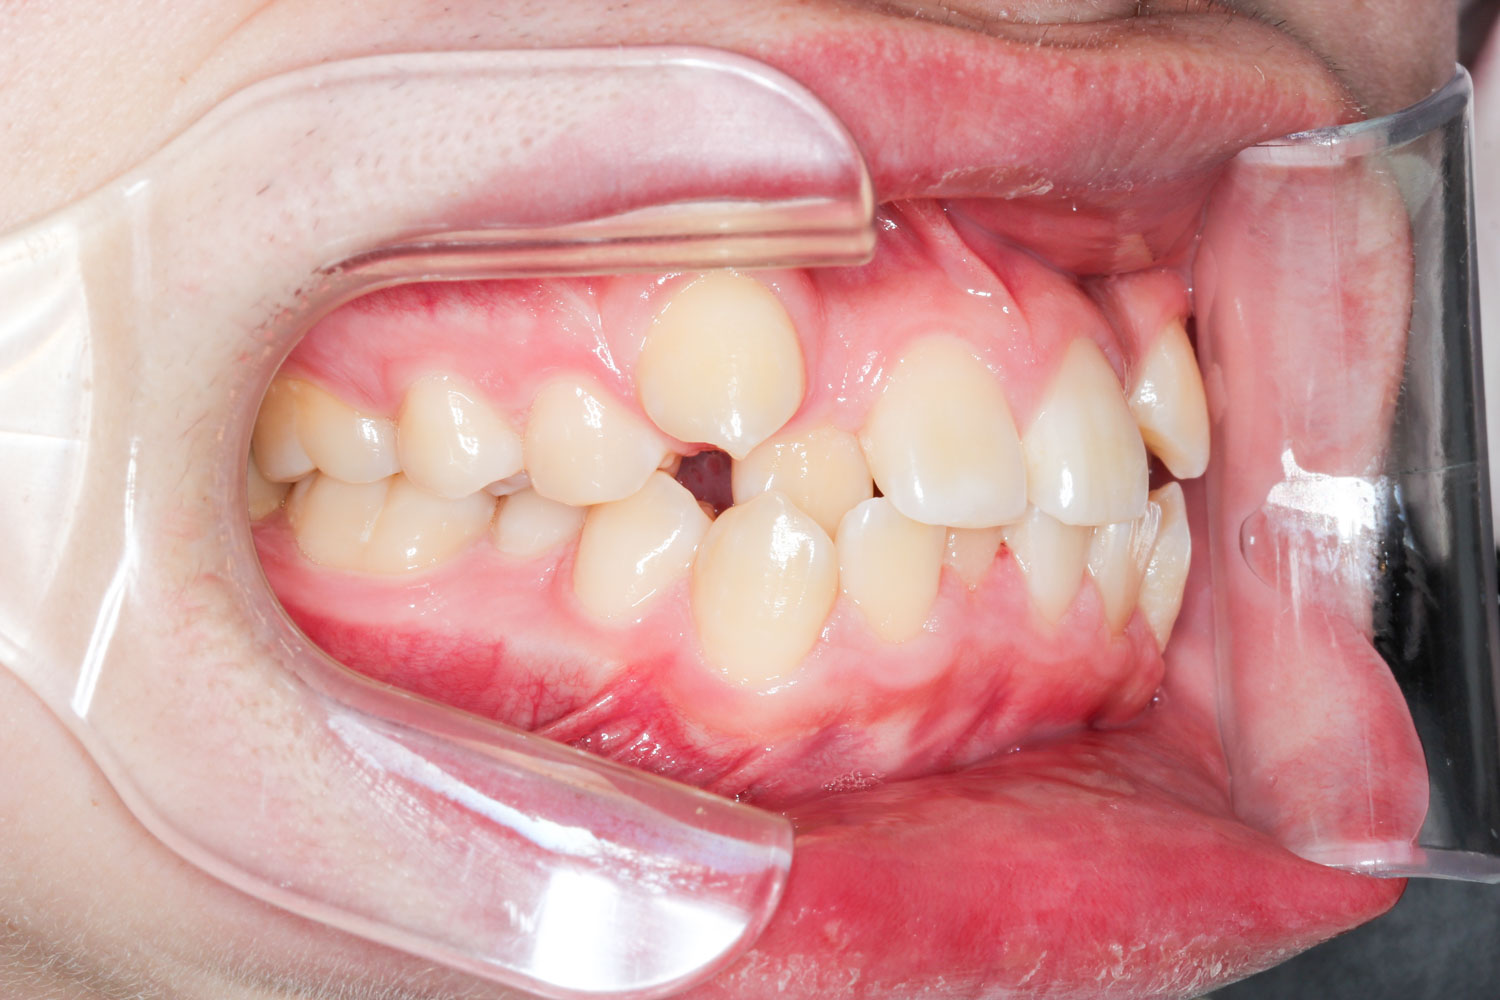

Before

After

年齢 10代

治療装置 表側の矯正装置(ホワイトコース)

治療内容 上下左右4本抜歯

治療期間 2年1か月

リスク 歯の移動に伴う痛み、歯肉退縮、歯根吸収、歯肉炎、虫歯

主訴 ガタガタが気になる

症状 叢生(ガタガタ)

治療回数 25回程度

総額費用 105万円程度